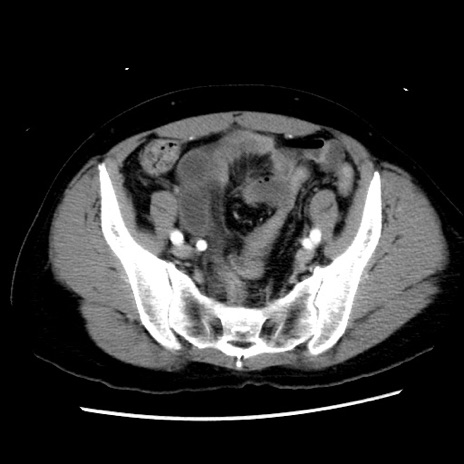

症例10(横断像)

【症例】 50歳代女性

【主訴】 腹痛

【現病歴】前日生レバーを食べた。今朝に排便あり。 昼前に突然発症の腹痛を生じ、当院救急外来を受診した。

【既往歴】 子宮筋腫にてで子宮全摘後

【身体所見】 意識清明、腹部:平坦、軟、下腹部やや左を中心に圧痛・反跳痛あり、筋性防御あり

【データ】WBC 7800、CRP 0.07